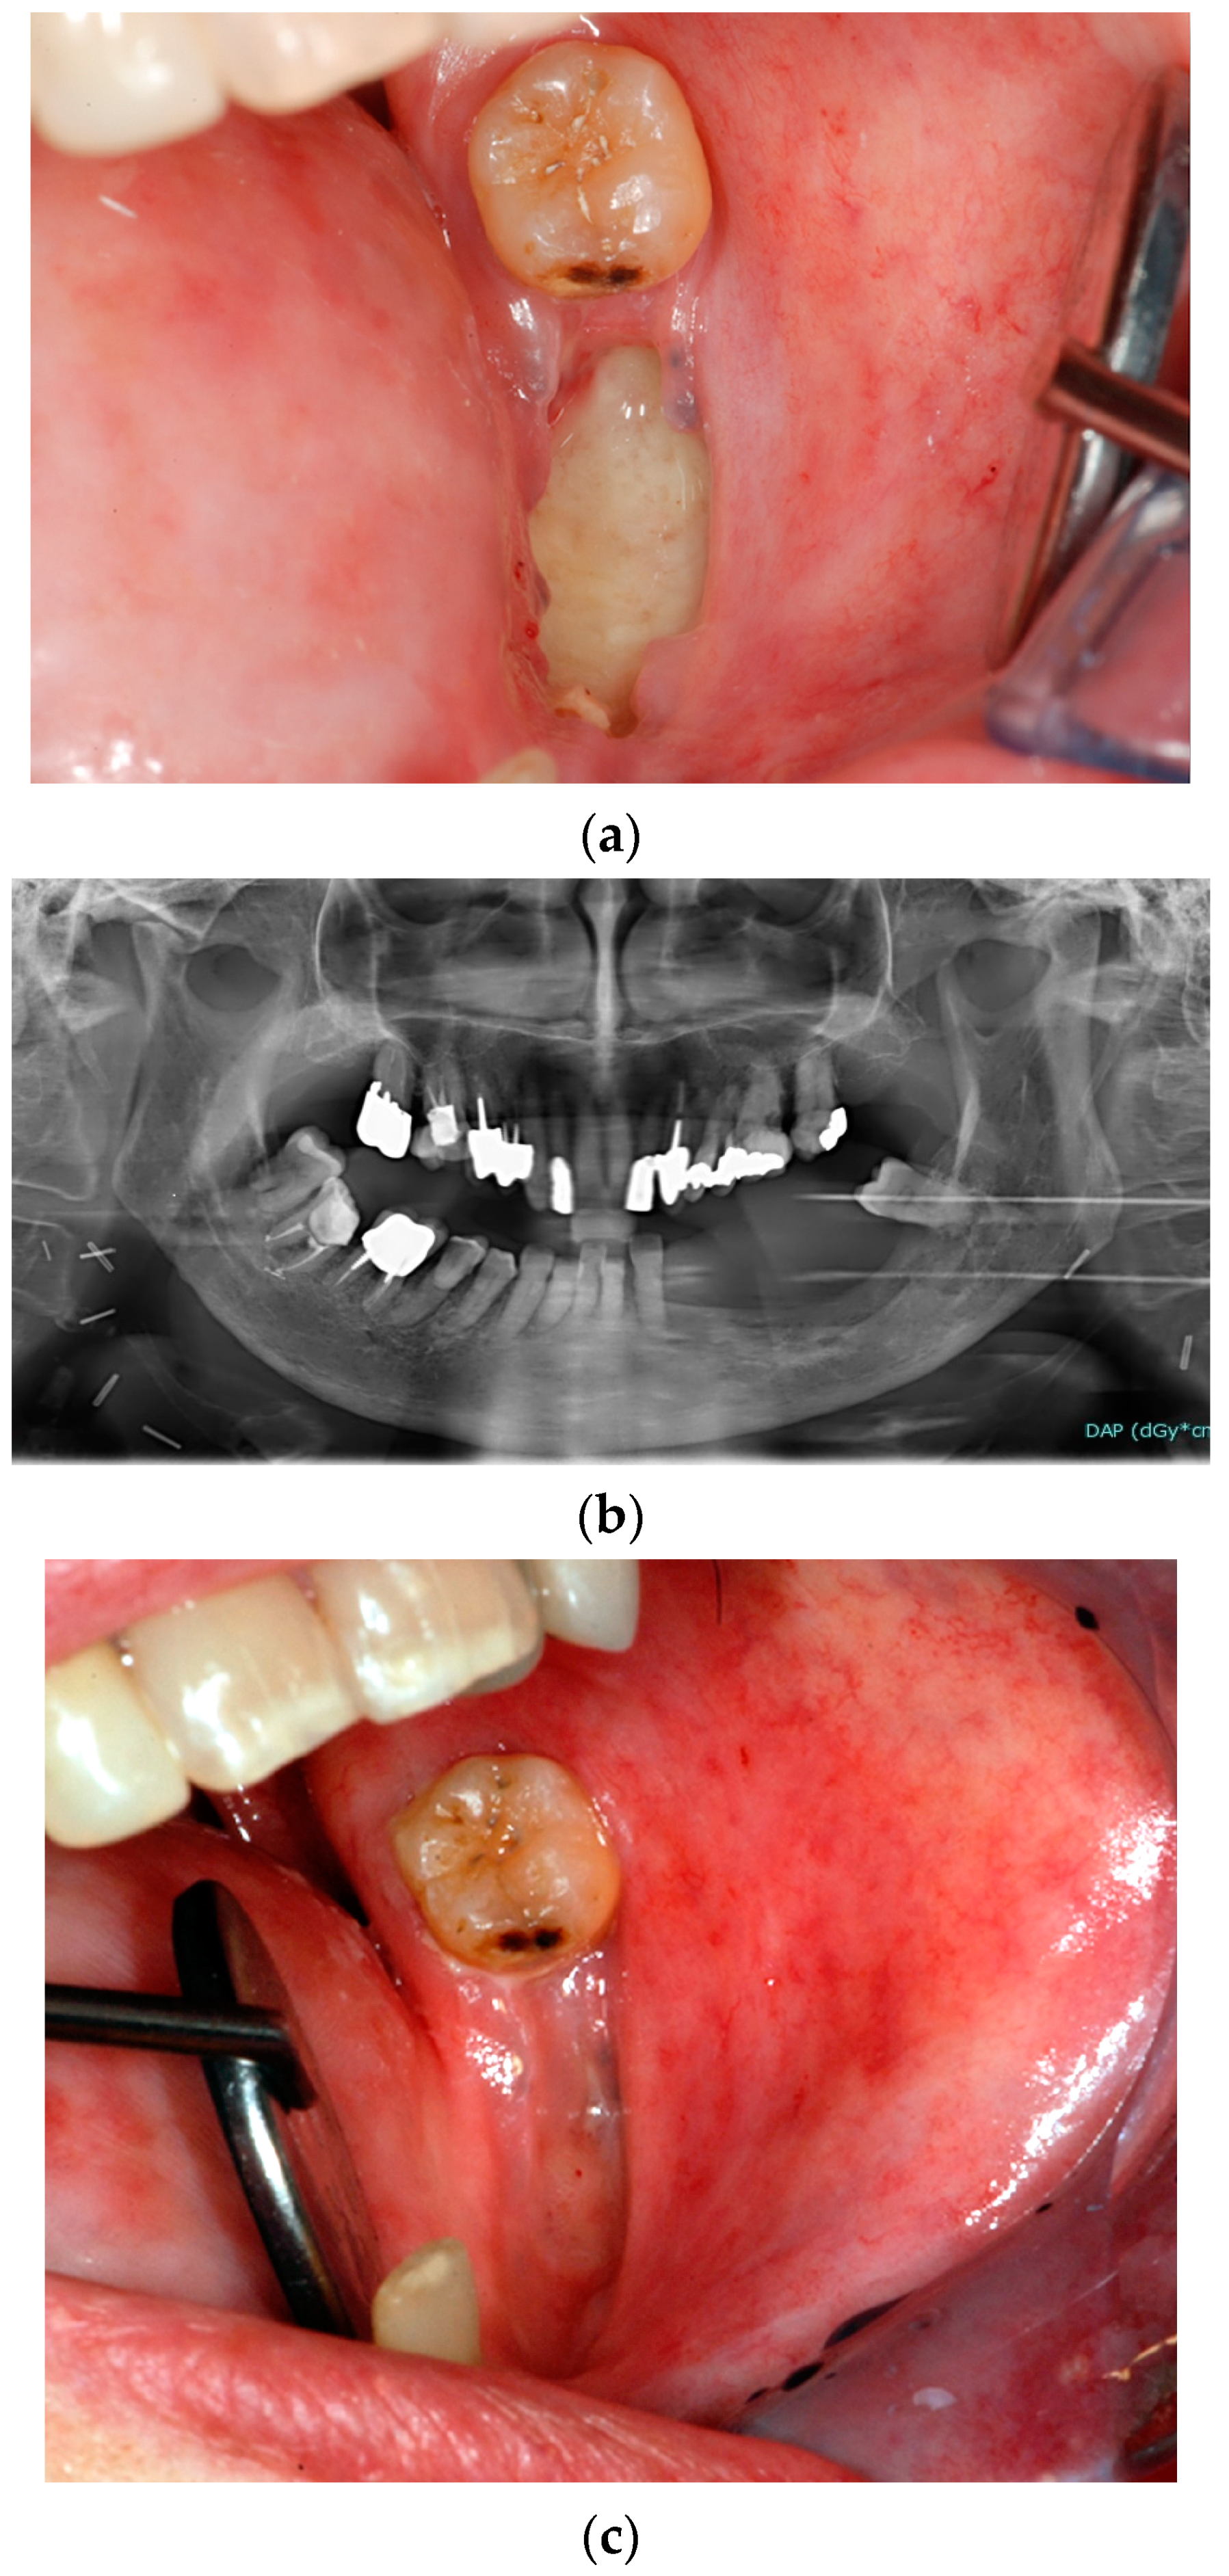

The use of the PENTO protocol as a therapeutic regimen has been reported for the management of ORN [81,82] in order to promote bone sequestration until spontaneous bone removal or to facilitate the following surgical procedures of bone sequestrectomy (Figure 1). Similarly, the PENTO protocol has been proposed for the management of medication-related ORN of the jaw (MRONJ) [83].

Figure 1.

Clinical case of a patient, who received RT for OSCC and developed ORN of the left mandible: clinical picture of the necrotic bone lesion (a) and related orthopantomography (b). The patient was treated with bone sequestrectomy under PENTO protocol: six months after conservative surgery for removing bone sequestration, the complete healing could be observed (c).